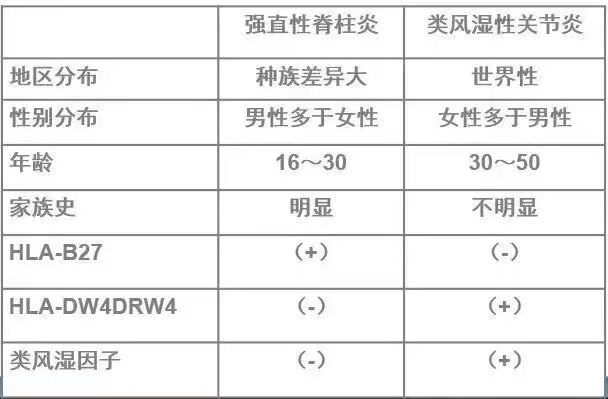

现已确认AS不是类风湿关节炎的一种特殊类型,两者有许多不同点可资鉴别。

表1:强直性关节炎和类风湿性关节炎的鉴别要点